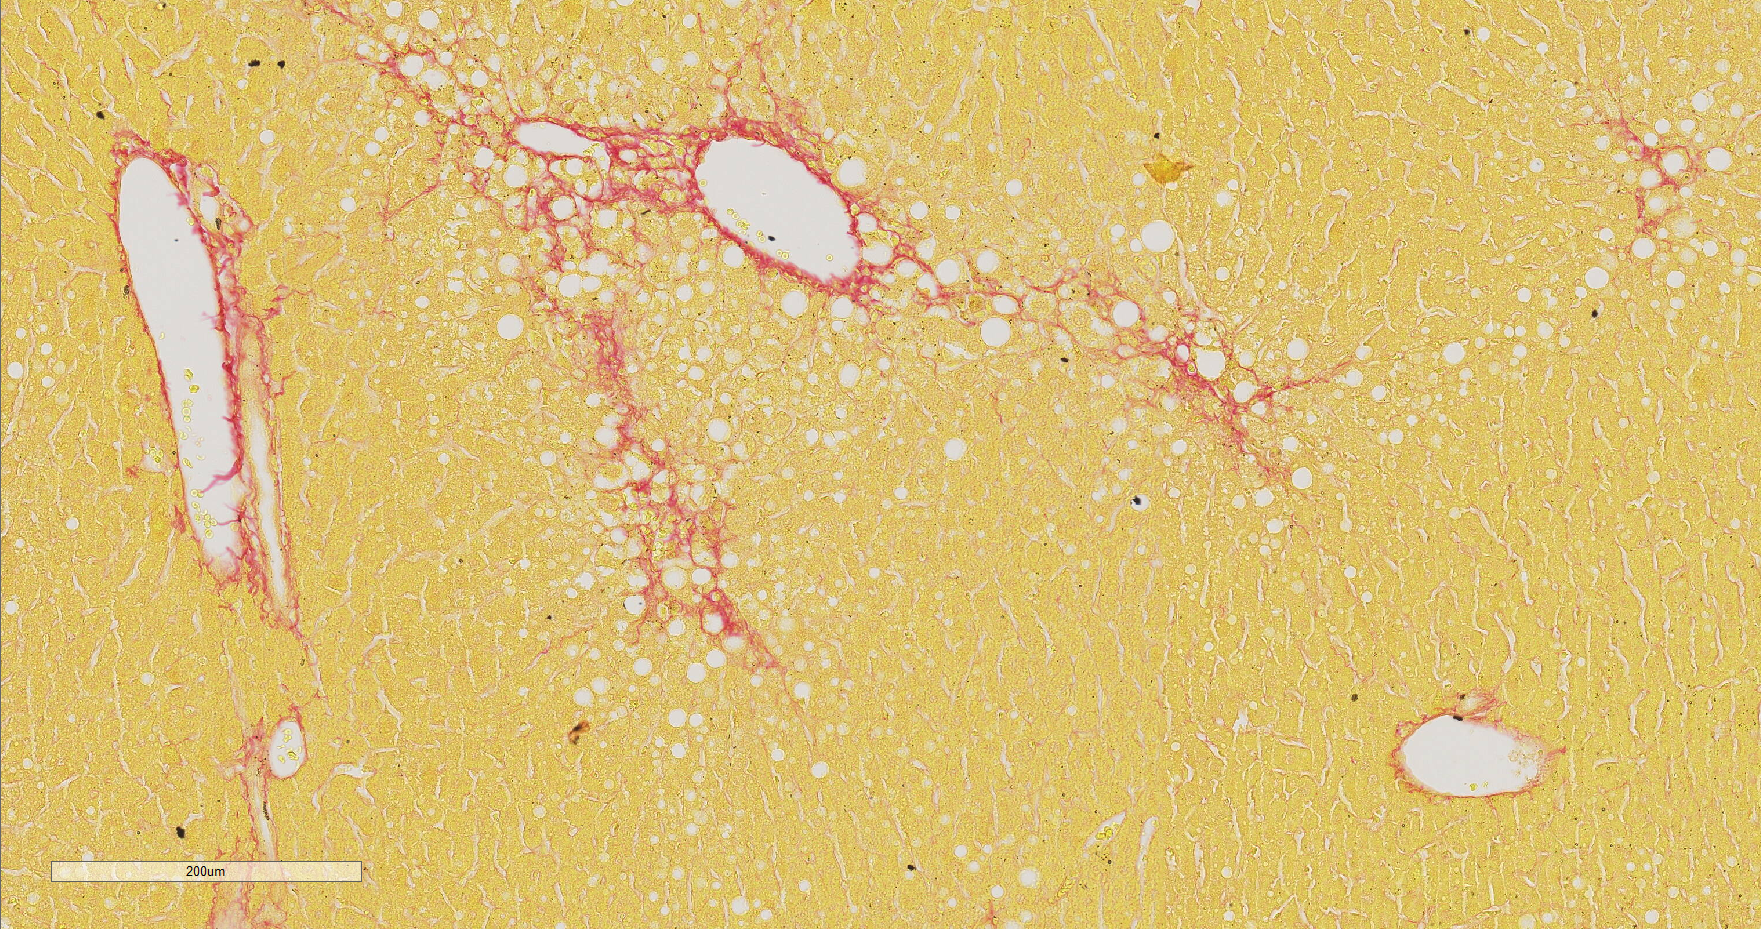

天狼星红染色

天狼星红与其衬染液都是强酸性染料,易与胶原分子中的碱性基团结合, 吸附牢固。偏振光镜检查,胶原纤维有正的单轴双折射光的属性,与天狼星红复合染色液结 合后,可增强双折射,提高分辨率,从而区分Ⅰ型和Ⅲ型胶原纤维。

非酒精性脂肪肝病模型 肝脏天狼星红染色